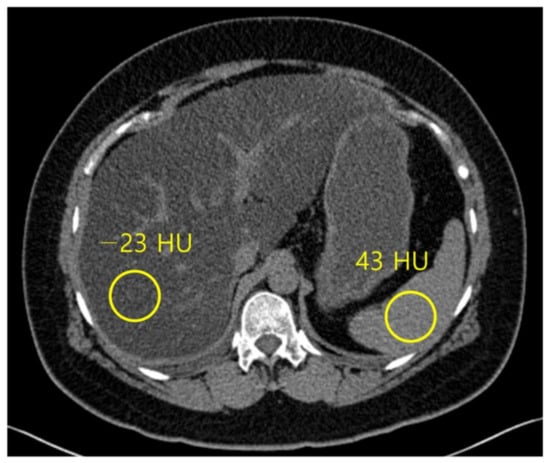

Figure 4.

Non-contrast computed tomography shows the attenuation of the liver and spleen. The mean attenuation of the liver (−23 HU) is remarkably lower than the mean attenuation of the spleen (43 HU), which represents severe hepatic steatosis.